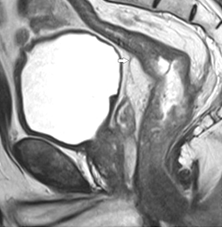

Измеряется расстояние до дистального края опухоли (рис. 1):

от анального края,

от уровня m. puborectalis (зубчатой линии / аноректального угла), соответствующего верхней границе хирургического анального канала.

Сагиттальная проекция является основной для оценки протяженности опухоли, ее положения относительно зубчатой линии (уровня верхнего края m. puborectalis) и переходной складки брюшины.